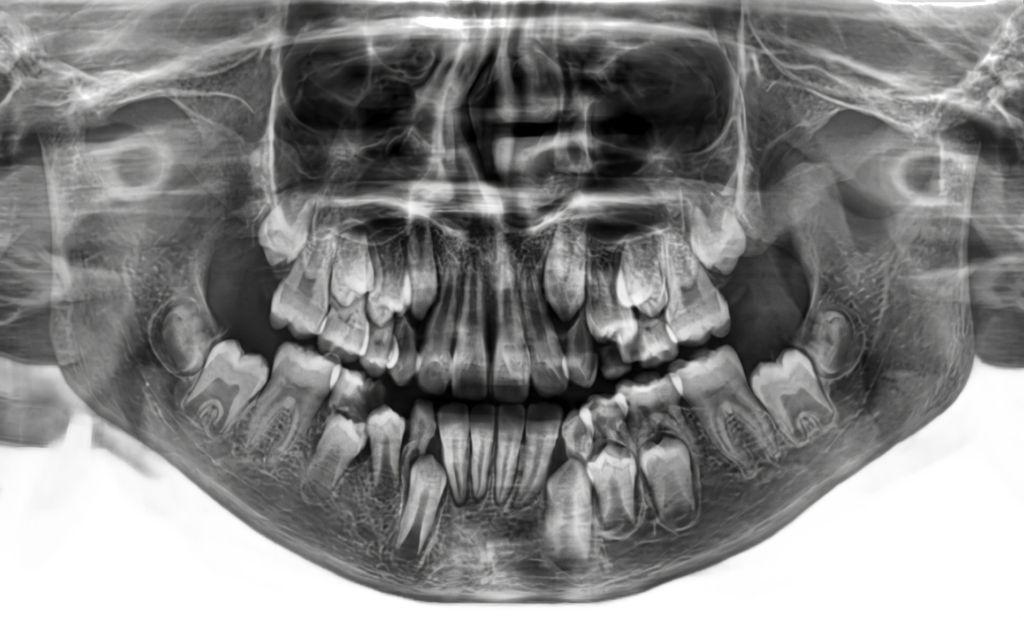

He is certified in Cone Beam Computed Tomography (CBCT) and has extensive experience in advanced radiological diagnosis. Dr. Singh is associated with several reputed centers across India as a consultant radiologist for CBCT reporting. His expertise includes implant planning, impacted teeth localization, oral and maxillofacial pathology interpretation, TMJ assessment, maxillary sinus evaluation, and airway analysis.